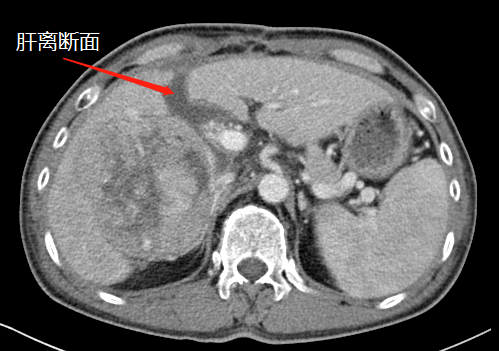

術(shù)前CT

近段時間,他因右上腹疼痛就診于瀘州市中醫(yī)醫(yī)院,在檢查中發(fā)現(xiàn)右側(cè)肝臟有一12公分左右的包塊,初步考慮為惡性腫瘤,后收治入院。通過全面檢查,診斷其為肝癌晚期,并伴有乙型肝炎、肝硬化等病癥。

“該患者入院后,通過肝臟CT,我們發(fā)現(xiàn),由于其右肝腫瘤巨大,而正常的左肝體積比較小,手術(shù)預(yù)切除肝體積達(dá)70%以上,術(shù)后殘肝體積僅28.3%,再加上該患者存在乙肝和肝硬化,剩余肝臟不足以維持他身體正常運(yùn)轉(zhuǎn)所需,不具備肝臟手術(shù)切除的基本要求。”胡偉表示。